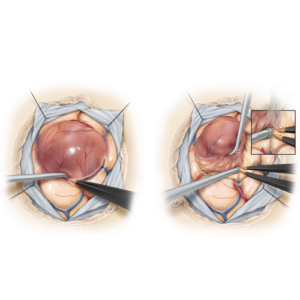

Laparoscopic & Robotic-Assisted Surgery

Laparoscopic & Robotic-Assisted Surgery

- Procedure:Minimally invasive colectomy (partial removal of the colon) or proctectomy (rectal cancer surgery).

- Ideal for: Stage 1B & Stage 2 tumors requiring deeper tissue removal.

- Cost: €24,000 – €65,000

- Prognosis: 80-90% survival rate when combined with adjuvant therapy (if needed).